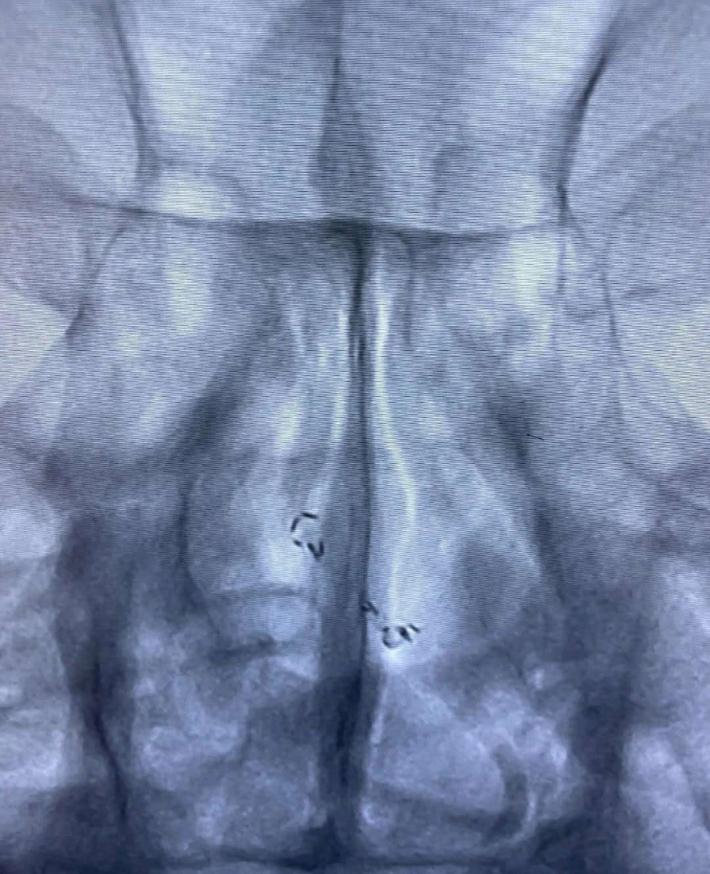

经反复收拉尝试,最终取出Enterprise 2支架。

Enterprise 2支架在血管内两端严重变形,反折的Mark恰好被Solitaire AB支架咬合取出。

Enterprise 2支架经过体外揉搓,恢复了形态,支架内一同取出的还有一大坨增生的支架内血栓。